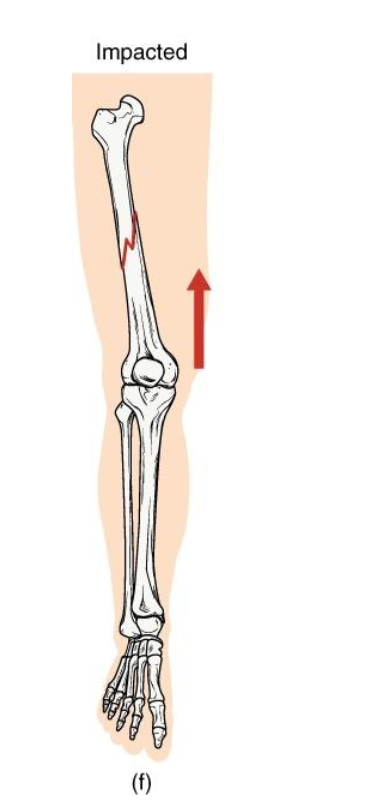

Impacted fracture

Definition: One fragment is driven into another within the same bone

Mechanism: Axial loading (ex: landing hard on extended arm/leg)

Clinical note: Bone ends jammed together; limb may apper shortened

Key concept: common in falls - the bone compresses itself

<p><strong>Definition: One fragment is driven into another within the same bone</strong></p><p><strong>Mechanism</strong>: Axial loading (ex: landing hard on extended arm/leg)</p><p><strong>Clinical note: Bone ends jammed together;</strong> limb may apper shortened</p><p><strong>Key concept:</strong> common in falls - the bone compresses itself</p>